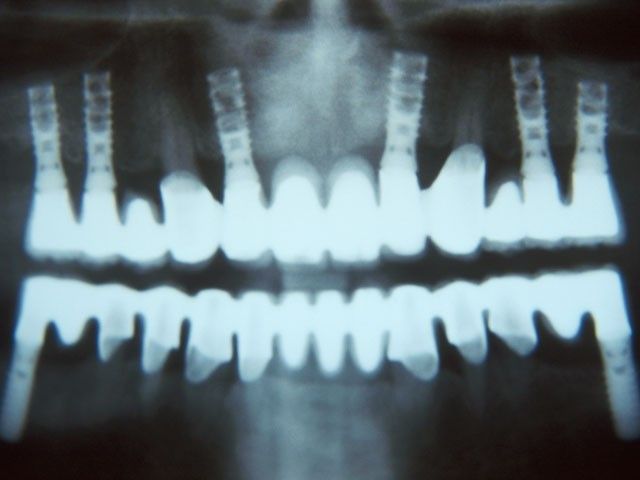

“Στις παρακάτω φωτογραφίες προβάλλονται δύο παλιά περιστατικά. Το πρώτο είναι το πρώτο μας εμφύτευμα και είναι το μακροβιότερο από όσα έχουν τοποθετηθεί στην Κρήτη! Το δεύτερο είναι μια μεγαλύτερη αποκατάσταση από το 1997”

ΔΕΥΤΕΡΟ ΠΕΡΙΣΤΑΤΙΚΟ